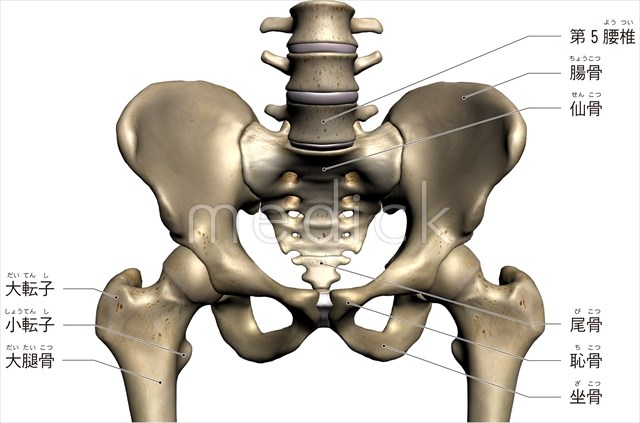

骨盤・股関節の解剖学 – McDavidサポータ-ブランドのマクダビッド オフィシャルサイト。

股関節の構造のイラスト - 医療のイラスト・写真・動画、素材販売サイトのメディック medick。